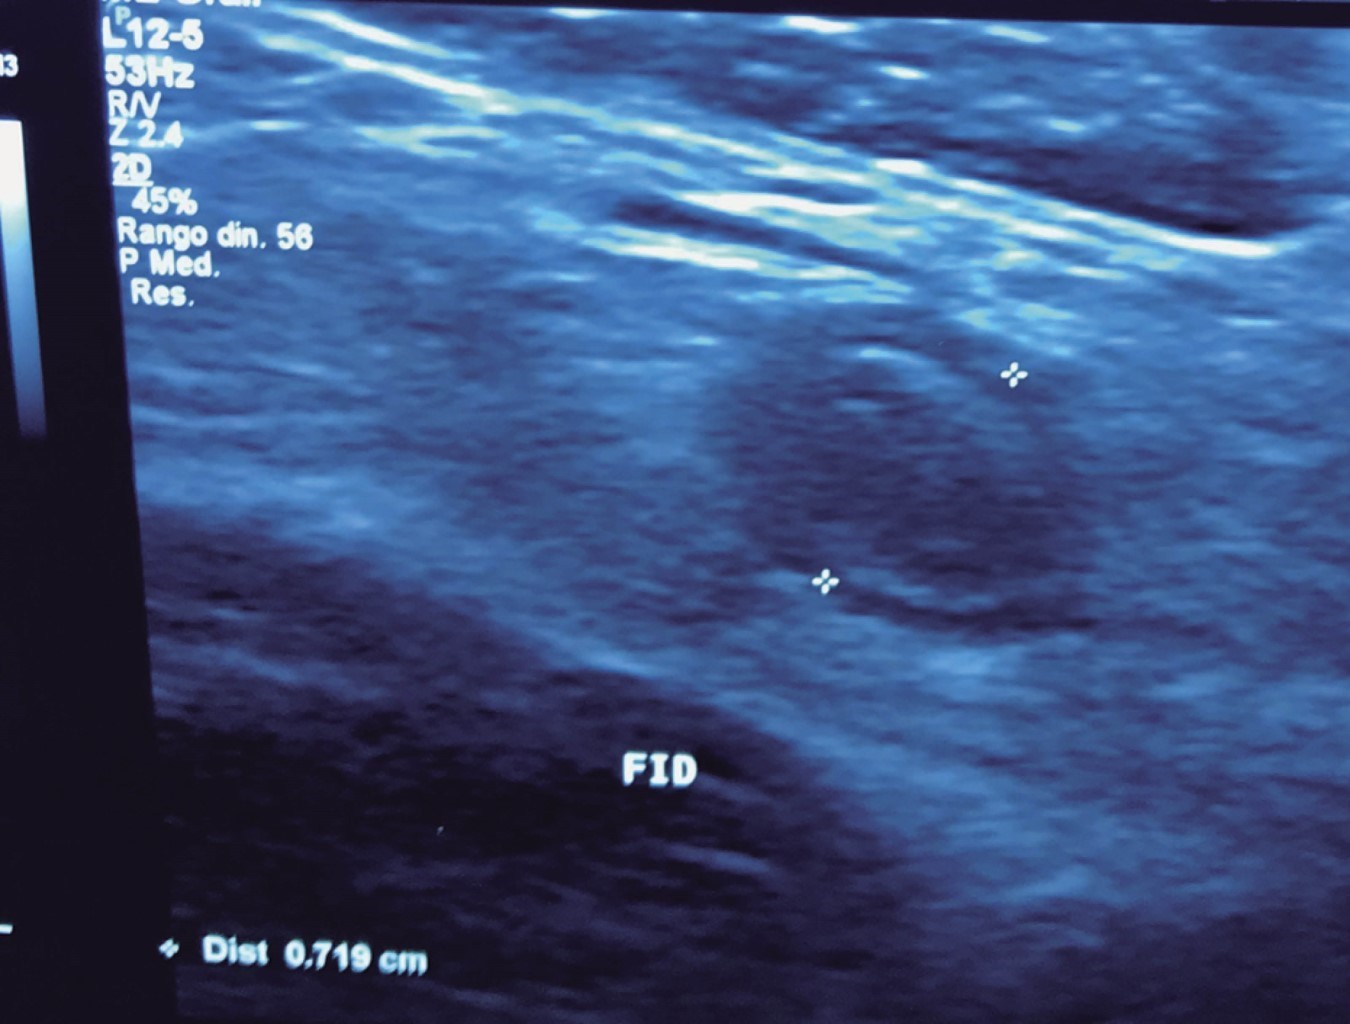

El cirujano general aborda particularmente problemas clínicos que incluyen el aparato digestivo, el cuello, la pared abdominal y los trastornos del sistema circulatorio y el tórax. Un artículo publicado en 2008, por Lindelius,15 demostró que la implementación del ultrasonido por parte del cirujano general en casos de dolor abdominal agudo incrementó en 7.9% la precisión diagnóstica. En la consulta cotidiana de la especialidad, incorporar el rastreo sonográfico al área explorada agrega minutos al examen clínico que aportan datos de notable valor por la objetividad y precisión. El abdomen suele ser el sitio que los cirujanos generales exploramos con más frecuencia. Es posible en una consulta cotidiana hacer todo el protocolo de ultrasonido de abdomen superior en minutos, que incluye ambos cuadrantes superiores y los flancos, pudiendo observar el hígado, la vesícula y los conductos biliares, ambos riñones, el bazo, parte del páncreas y, con ayuda del Doppler color, los principales vasos de la región como la vena cava inferior, la aorta abdominal, la vena porta, los vasos esplénicos y la arteria hepática. Puede haber limitantes como el contenido gástrico, el nivel de llenado de la vesícula biliar o la constitución del paciente y su capacidad de cooperar con el estudio. Pero con la práctica cotidiana, se adquieren las destrezas y el refinamiento suficientes para lograr, con la experiencia acumulada, producir imágenes de relevancia diagnostica inmediata. En la fase de entrenamiento, contrastar nuestros hallazgos con información disponible en la red, con los colegas imagenólogos, o cirujanos ya experimentados en ecografía, permitirá la retroalimentación y la tutoría esenciales de toda curva de aprendizaje. Tradicionalmente se consideraba que aquellos órganos que contienen una mezcla de líquido y gas (intestino, estómago) no son valorables por ultrasonido, el gas produce un efecto rarefacción, ya que no comprime las ondas como un tejido solido o un medio líquido, la señales entonces se dispersan impidiendo que regresen como ecos y permitan al procesador formar una imagen congruente con el órgano explorado. Sin embargo, cuando esta condición cambia como consecuencia de un estado patológico, es posible identificar el contenido intestinal o el gástrico y darnos una idea más aproximada de lo que realmente está ocurriendo en ese abdomen. Podemos, por ejemplo, saber si un estómago está lleno de líquido, o si el intestino contiene residuo sólido, líquido o gaseoso. Los equipos actuales pueden incluso ver en detalle la pared intestinal cuando ésta esté dilatada. Se puede distinguir cuando el colon está ocupado de líquido a nivel del flanco izquierdo como podría ser en una colitis amebiana o en una oclusión intestinal,16 donde se observa dilatación del intestino delgado ≥ 25 mm, el peristaltismo anormal, la presencia de líquido libre intraperitoneal y el edema de la pared intestinal (Figura 2). En casos de dolor abdominal agudo, el ultrasonido puede, en forma inmediata, permitir diagnósticos diferenciales como el hallazgo de una dilatación pielocalicial por nefrolitiasis (Figura 3), o un aneurisma de la aorta abdominal (Figura 4). Un estudio prospectivo realizado en Irvine, California,17 encontró que la a capacidad diagnóstica del médico de primer contacto practicando el ultrasonido para detectar una colelitiasis tiene una especificidad de 87% y una sensibilidad de 82%, mientras que la prueba de ultrasonografía realizada por radiología tuvo sensibilidad de 83% y una especificidad de 86%. Es decir, que, ahorrando tiempo al paciente, el diagnóstico de colelitiasis es factible agregando unos minutos al examen físico inicial. En casos de apendicitis, el método diagnostico considerado como el estándar de oro es la tomografía axial computarizada (TAC). Sin embargo, tiene inconvenientes como su disponibilidad, su costo, el riesgo de radiación en niños y pacientes embarazadas. En tales situaciones, sobre todo en niños, sexo femenino o pacientes delgados, el ultrasonido es una poderosa herramienta que complementa el examen clínico inicial. Las ventajas del ultrasonido frente a la tomografía serian su ubicuidad (ya está en la sala de emergencias), el bajo costo, la ausencia de radiación y el diagnóstico diferencial con causas ginecológicas o genitourinarias de dolor. En apendicitis, la sensibilidad y especificidad de la TAC es de 99.4% y 80.0%, respectivamente. Para el ultrasonido, la sensibilidad diagnóstica es de 83% y la especificidad de 90%. La tasa de apendicectomía negativa es ligeramente mayor en el grupo de TAC que en el del ultrasonido, es decir, 7.1% (3/42) (TAC) en comparación con 4.67% (5/107) (ultrasonido). Hay que recalcar que el ultrasonido es operador dependiente. La experiencia y la calidad del equipo juegan un papel importante.18 La apendicitis tiene varios hallazgos característicos, como la pared edematosa y el aumento de grosor general. Se toman para criterios de positividad una estructura tubular aperistáltica no compresible que mide más de 6 mm de diámetro en el cuadrante inferior derecho (Figura 5).19-21

Figura 4